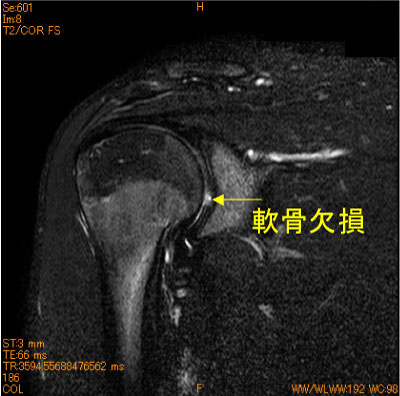

関節窩中央の軟骨欠損-肩関節MRI-

10代男性、投球時の痛み。

投球障害では、後上方関節唇損傷、棘下筋腱関節側部分断裂、Bennett lesionが知られているが、何があるか判らないの肩関節の障害である。

脂肪抑制T2 WIは不可欠のシークエンスである。

![]() Obl. Cor T2WI 脂肪抑制 |